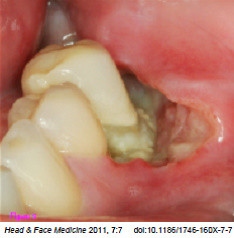

Οι πιο συχνές βλάβες στο στόμα είναι τα αποστήματα, τα οποία όταν οφείλονται σε μικροβιακές λοιμώξεις δοντιών της άνω γνάθου μπορούν να εκδηλώνονται και στην υπερώα (Εικόνα 3). Η θεραπεία τους προϋποθέτει την θεραπεία του υπεύθυνου δοντιού.

Εικόνα 3. α. Απόστημα που οφείλεται σε γομφίο οδόντα (βέλος), β. Απόστημα που οφείλεται σε τομέα οδόντα (βέλος).